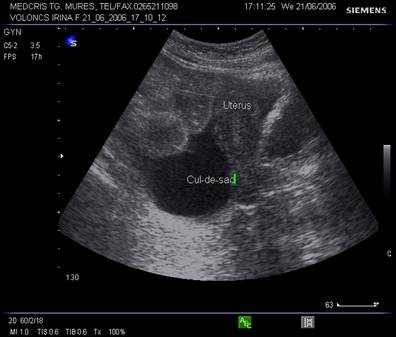

Fig. nr.408.Zona anecogena in sacul Douglas , la ecografia abdominala, asociata ascitei